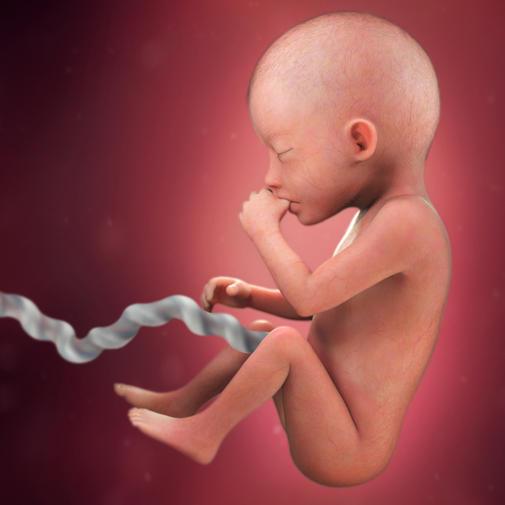

Rychlý růst plodu do délky pokračuje i v těchto týdnech. Výrazně rostou do délky dolní končetiny a vyrovnávají tak své předchozí zpoždění.

Na tělním povrchu jsou velmi jemné chloupky – lanugo. Jemné chloupky lanuga najdeme zpočátku i na dlaních a na chodidlech, před koncem gravidity ale vymizí.

Na povrchu kůže dlaní a chodidel jsou již jasně vykreslené obrazce kožních rýh. Jejich uspořádání je pro každého člověka charakteristické, dědičně dané a po celý život neměnné.

Pohyby plodu jsou důraznější. Ručičky ohmatávají okolí. Paleček se dostane občas do úst a plod jej rty a jazykem dumlá. Nožičky vydatně kopou.

Volný pohyb plodu ve všech směrech zajišťuje pupečník, jehož délka dosahuje asi 50 cm. Cévy, které zásobují plod kyslíkem, živinami a dalšími důležitými látkami, probíhají v pupečníku spirálovitě. To je chrání před poškozením při natažení pupečníku.

Srdeční akce je velmi rychlá, srdce plodu tepe dvakrát rychleji než srdce matky.

V amniovém vaku je asi 350 ml plodové vody. Vzhledem k tomu, že plod roste v této době rychleji, než se zvětšuje děloha, začíná docházet k jeho občasným kontaktům s děložní stěnou – těhotná žena vnímá pohyby miminka.

Dítě je uprostřed svého prenatálního vývoje. Kůže je složená ze čtyř vrstev, je již pevnější, než tomu bylo například před dvěma týdny. Dozrávají spoje a nervové buňky v centrální nervové soustavě, které odpovídají na podněty smyslových orgánů. Holčičkám se právě v tuto dobu formuje pochva, v jejích vaječnících je nyní založeno na 2 miliony vajíček, kterých však v době narození zůstane polovina. Vývoj smyslů je nyní ve svém klíčovém stadiu. Dítě je stále drobné, ale rychle roste. Užívá si protahování končetin.

Od 20. týdne těhotenství se pro určení délky plodu používá součet délky hlavičky, trupu a nohou. Ve 20. týdnu těhotenství měří plod zhruba 25,5 cm. Váha plodu je nyní zhruba 300 g.